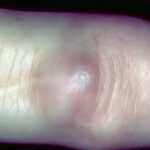

MYXOID CYST

Myxoid cyst appears as a nodule of the proximal nail fold associated with a longitudinal groove in the correspondent nail plate. Because the cyst often drains spontaneously, the shape of the groove is irregular . Myxoid cysts usually affect the fingernails of middle-aged women and are associated with osteoarthritis of the interphalangeal joints.